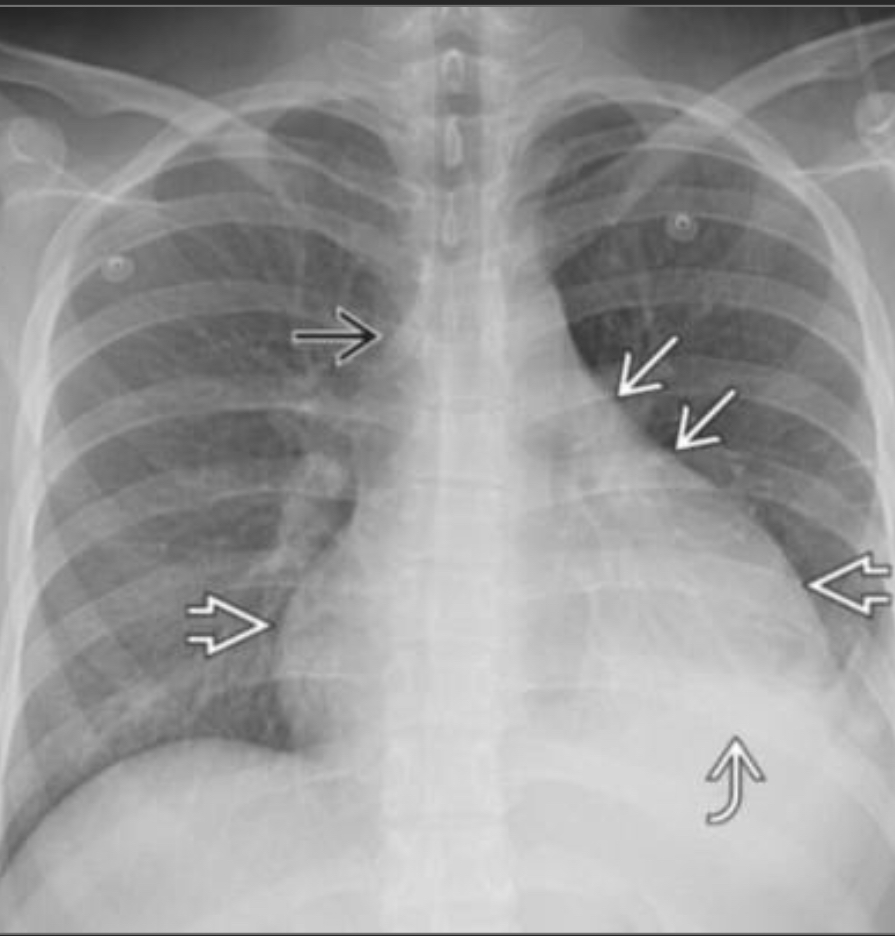

chronic hypersensitivity pneumonitis

Mosaic pattern with areas of ground-glass atenuation and areas of low attenuation.

Fibrosis and parenchymal distortion in a mid zone distribution.

left vs right?

Left UIP w honeycombing

Right Chronic HP